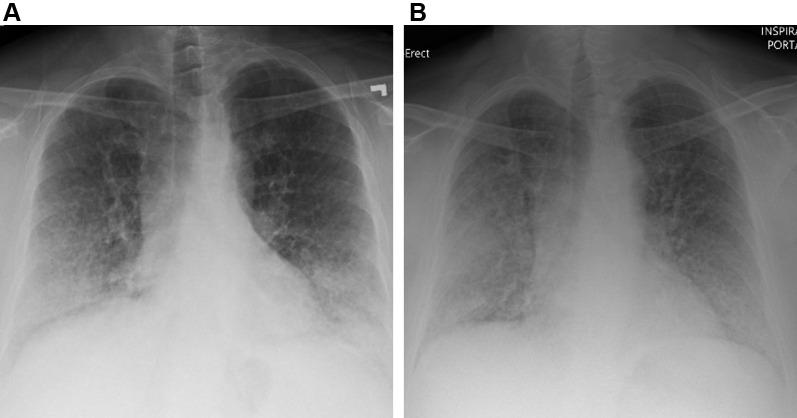

A 51-year-old Puerto Rican woman, with a known but inconclusive diagnosis of interstitial lung disease (ILD) since 2002 and recent moderate COVID-19, is now presenting with subacute worsening dyspnea on exertion. The patient had sporadic medical care over the years for her ILD (Table 1). Prior workup included chest CT imaging with a "crazy-paving" pattern of lung disease, as defined by ground-glass opacity with superimposed interlobular septal thickening and visible intralobular lines. Bronchoscopy showed normal airway examination, and BAL revealed clear fluid with foamy macrophages and negative cultures. Video-assisted thoracoscopic surgery and transbronchial biopsy specimens both showed foamy macrophages. Results of pulmonary function testing (PFT) revealed an isolated gas transfer defect on diffusing capacity of the lungs for carbon monoxide (Dlco). She had lived with mild yet nonprogressive functional impairment and stable exercise intolerance over these years. She was then hospitalized for COVID-19 in August 2020 and for recurrent shortness of breath in September 2020. She now presented 4 months following her September 2020 hospitalization.

一位 51 岁的波多黎各女性,自 2002 年以来已知但不确定的间质性肺病(ILD)诊断,以及最近中度 COVID-19,现在出现亚急性进行性呼吸困难。患者多年来一直间歇性地接受 ILD 的医疗护理(表 1)。之前的检查包括胸部 CT 成像,呈现出“铺路石样”的肺部疾病模式,定义为磨玻璃影伴小叶间隔增厚和可见小叶内线。支气管镜检查显示气道正常,BAL 显示澄清液体,含有泡沫状巨噬细胞,培养结果为阴性。胸腔镜手术和经支气管活检标本均显示泡沫状巨噬细胞。肺功能检查(PFT)结果显示一氧化碳弥散量(Dlco)的肺部气体转移缺陷孤立。多年来,她一直患有轻度但无进展的功能障碍和稳定的运动不耐受。然后,她于 2020 年 8 月因 COVID-19 住院,并于 2020 年 9 月因反复呼吸急促再次住院。现在,她是在 2020 年 9 月出院后 4 个月出现的。